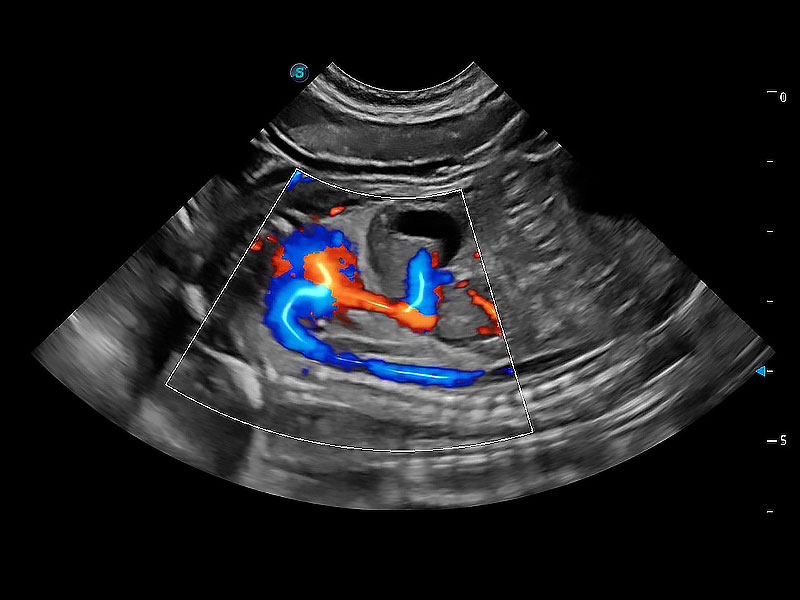

極大提升超低速微細(xì)血流的檢出能力,同時(shí)更精準(zhǔn)地濾除軟組織和超聲信號(hào),為獸用醫(yī)生提供以往無法通過常規(guī)血流獲得的疾病診斷信息。

在傳統(tǒng)二維血流成像的基礎(chǔ)上,呈現(xiàn)血流的立體感,具有動(dòng)感的生命力之美。即便是微小的血管也能輕松應(yīng)對(duì),提高了血流的視覺敏感性。